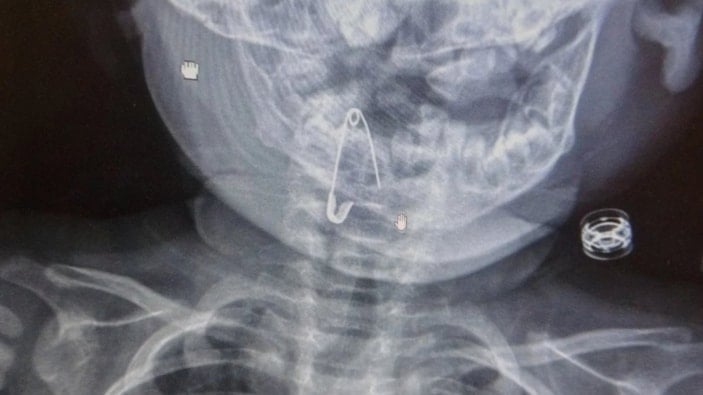

Öksürmeye başlayan minik çocuğun, hastanede çekilen röntgen sonucu çengelli iğneyi yuttuğu fark edildi.

8 aylık bir bebek, Bitlis’in Güroymak ilçesinden tarafımıza danışıldı. Güroymak ilçesinde çekilen röntgen sonucunda çengelli iğnenin soluk borusunun girişinde olduğunu teyit ettik. Yapılan müdahaleler sonucunda çengelli iğneyi çıkardık. Çıkardıktan sonra iki saat kadar gözlem altında tuttuk hastamızı. Daha sonrasında herhangi bir komplikasyonla karşılaşmadık ve sorunsuz bir şekilde taburcu ettik.